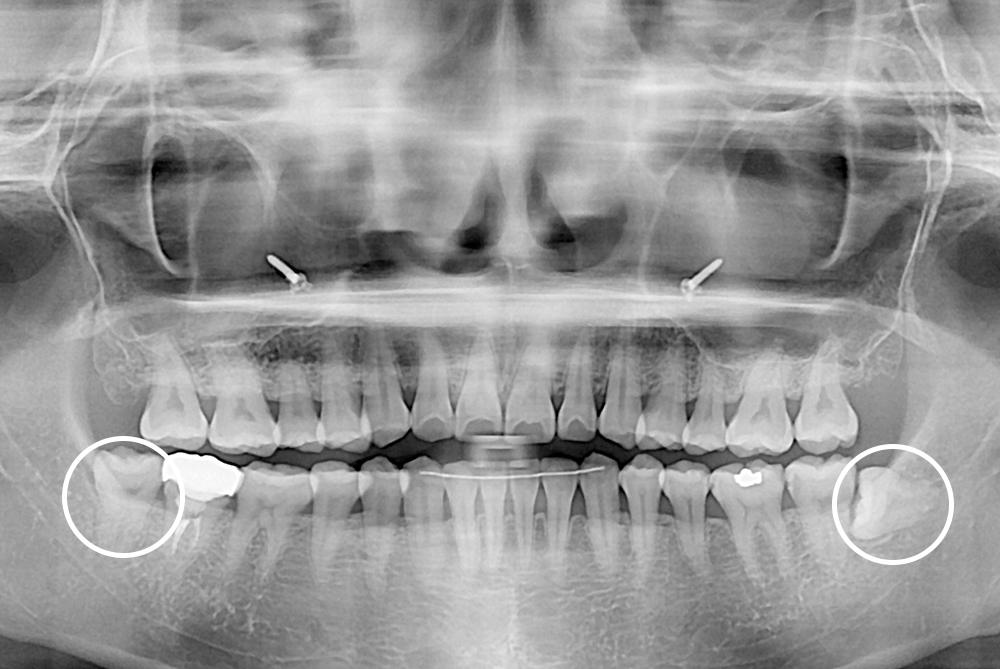

[사랑니] 매복 사랑니 발치

치료후 : 2020-01-30

세종치과는 구강악안면외과학 박사이신 원장님이 발치하는 치과입니다.